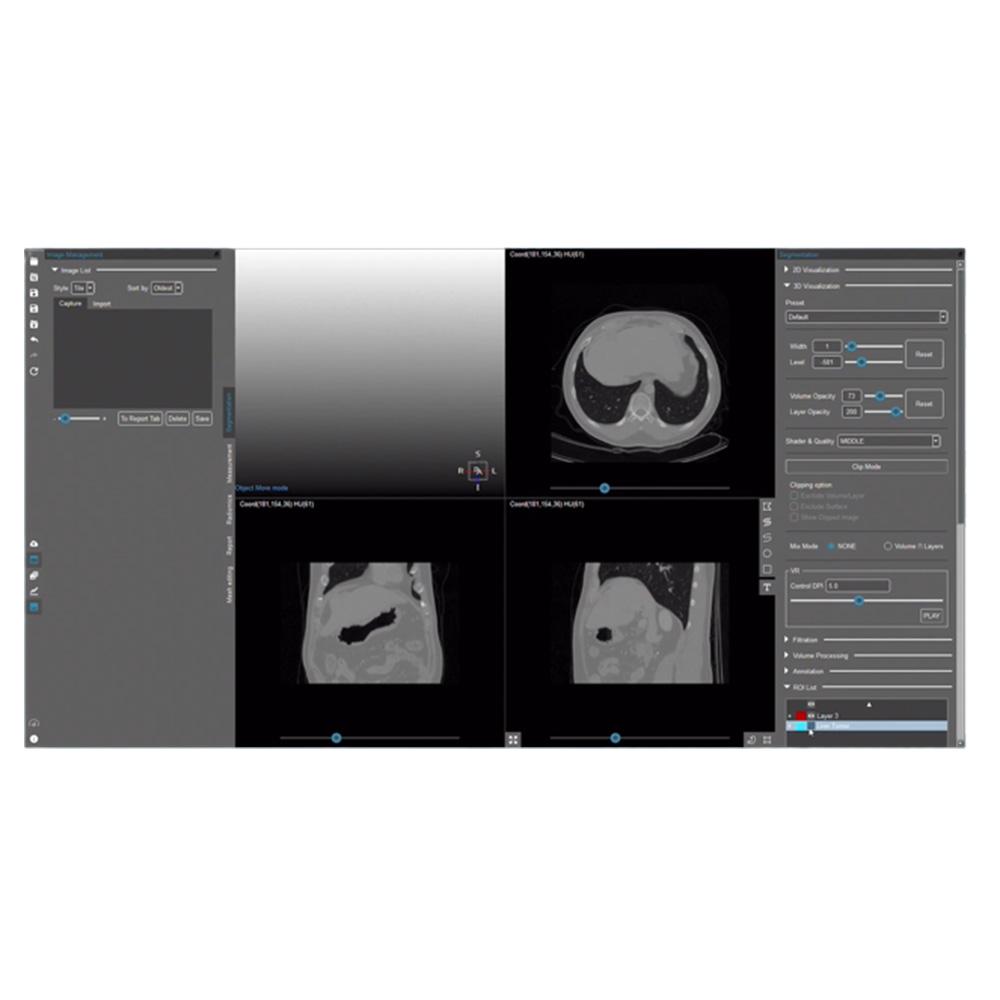

MEDIP PRO is a comprehensive software that processes medical images, enabling image analysis, 3-dimensional construction, modeling, and design with its automatic artificial intelligence (AI) segmentation technology at its core.

MEDIP PRO is equipped with One-Click Segmentation, which helps auto-segmentation

and extracts virtually all human body components in medical images (CT and MR) including patients’ organs and pathologic lesions.

and extracts virtually all human body components in medical images (CT and MR) including patients’ organs and pathologic lesions.